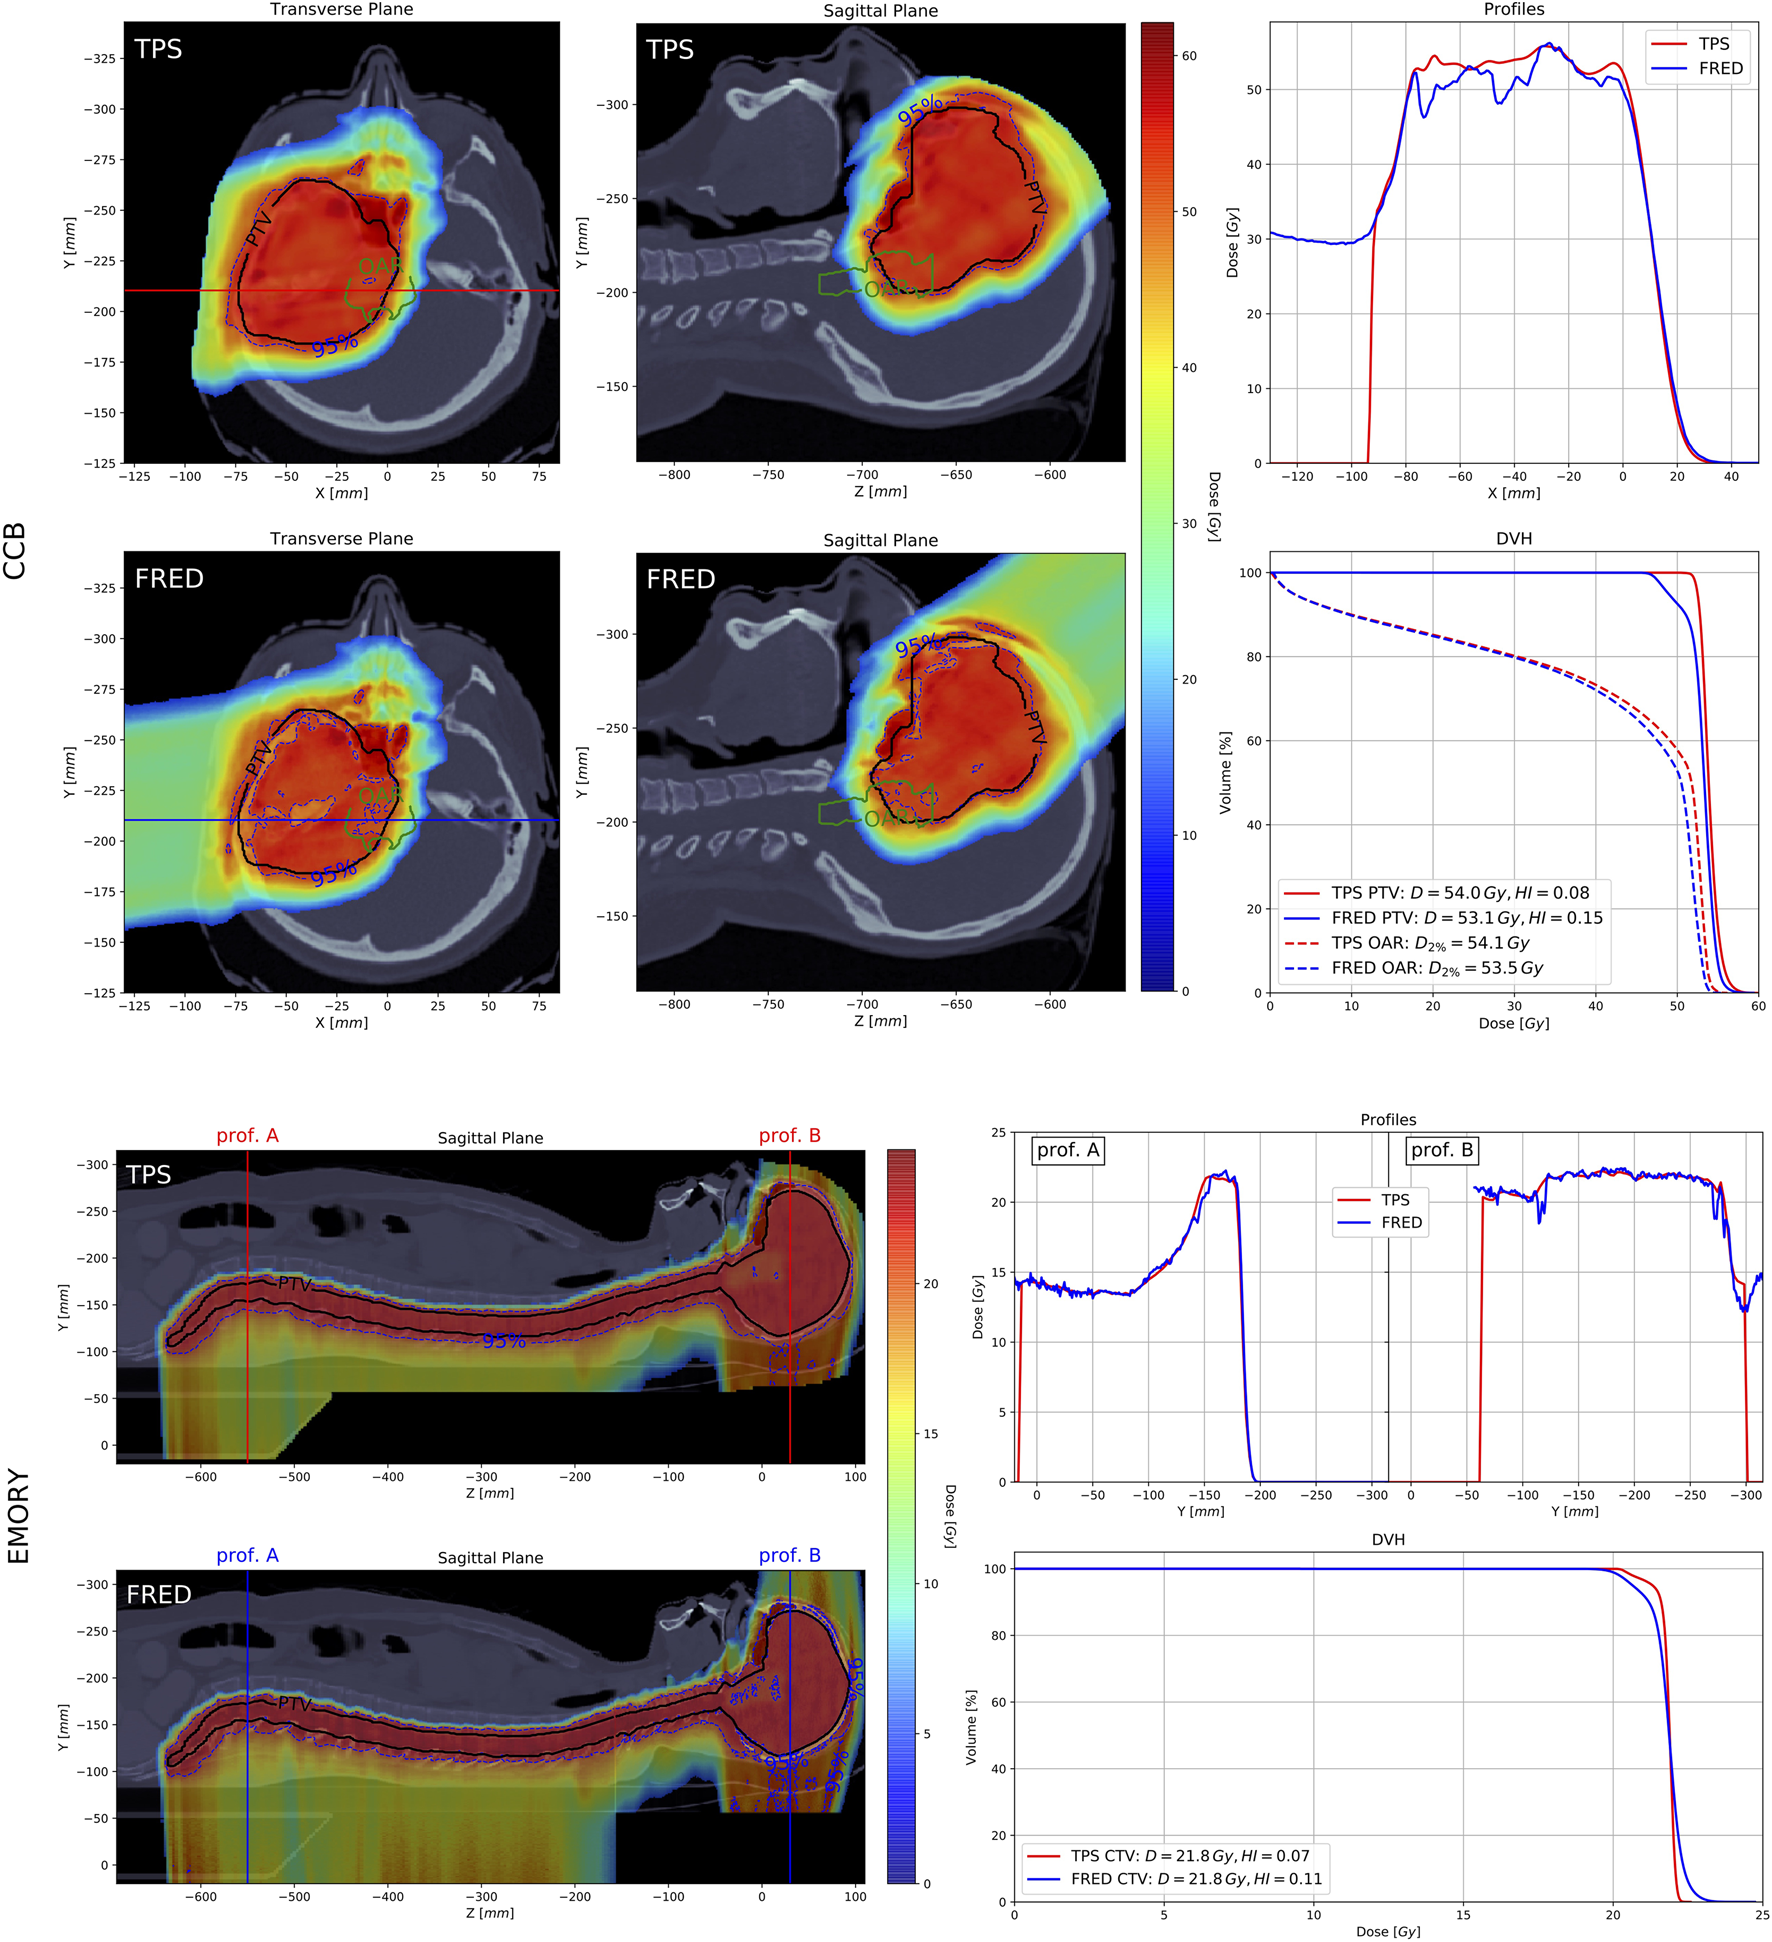

As an example, dose distributions, dose profiles, and DVHs recalculated with Fred and clinical TPS, for one patient case from CCB and one from EMORY, are shown in Figure 12. For CCB patient case (Figure 12 top panels), dose distributions computed with Fred are less uniform compared to the analytical TPS calculations. This is also observed analyzing the dose profiles and the DVH for PTV and results in the reduction of the mean dose in PTV and organ at risk. For EMORY patient case (Figure 12 bottom panels), the differences in dose distributions are less visible as MC-based TPS was used for the dose optimization and calculation. The observed differences between Fred and RayStation MC-based TPS are similar to the results obtained comparing RayStation with ECLIPSE MC algorithm reported by Chang et al. [7].

FIGURE 12. The evaluation of the treatment plan of patient treated at CCB (top panels) and at EMORY (bottom panels). On the left panels, dose distributions computed with clinical TPS and Fred are shown. PTV (black solid line) and 95% isodose (blue dashed line) are delineated. The corresponding dose profiles and DVHs are shown in top-right and bottom-right panels, respectively.